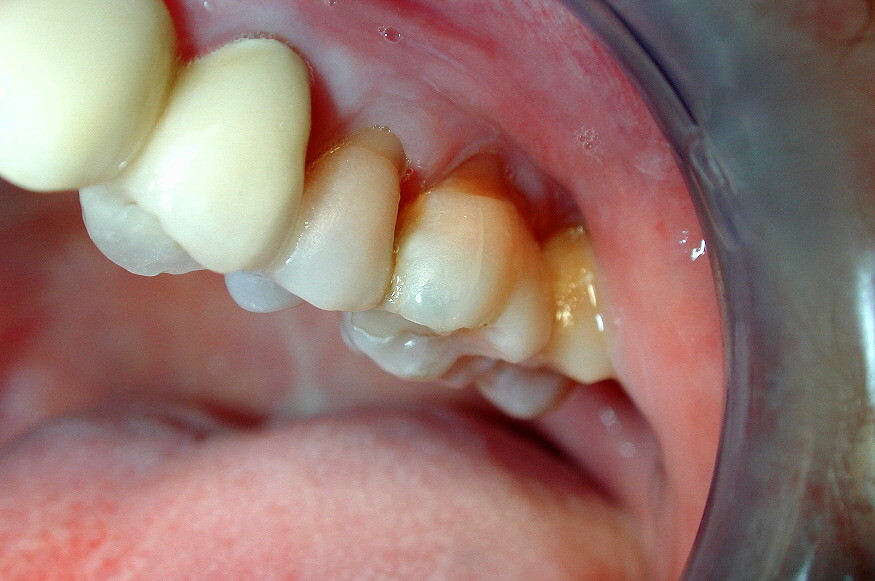

Many Surprising Reasons to See an Orthodontist

Everyone knows that you need to see an orthodontist to straighten your front teeth and have a nice smile—but there are other reasons that you may benefit from a visit to the orthodontist. Here are some of them:

There are many reasons for orthodontia besides a nice smile

First, orthodontists spend as much or more time getting a proper fit of the back teeth as they do with the front teeth. Getting the posterior teeth to mesh properly is important for the longevity of the dentition.

Poorly aligned back teeth are more susceptible to adverse tooth wear. In extreme cases, repairing these worn teeth can require root canal therapy and crowns

Second, crooked teeth are more at risk for periodontal or gum disease. Conditions such as crossbites can put adverse forces on teeth that can make them become loose and cause recession of the gum tissue.

Periodontal disease becomes worse if there is traumatic occlusion. Teeth that have tipped into spaces for missing teeth also have compromised gingival health.

The orthodontist can correct the alignment of the teeth and ensure that the forces when biting are optimal.